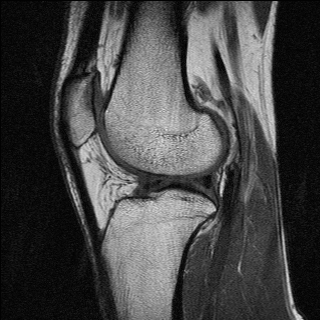

Figure 2.10: Sagittal MRI scans of the author’s knee with different contrasts. Left: T1 (TE=15 ms and TR=517 ms). Right: spin density (TE=11 ms and TR=2630 ms).

T1-weighted MRI images present a good contrast between fat, which appears dark, and water, which appears brighter. This type of contrast is used, for instance, in brain imaging to distinguish gray matter from white matter. Pathologies are often revealed by T2-weighted MRI. Edemas (abnormal accumulation of fluids) appear bright, while tumors often appear darker than normal tissues.

Examples of T1 and spin-density weighted images are shown in Figure 2.10.